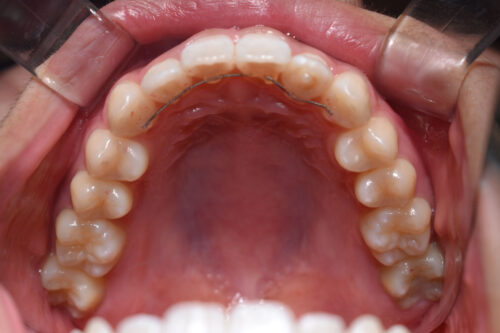

ワイヤー矯正治療7か月後です。

歯科矯正用アンカースクリュー(デュアル・トップオートスクリュー)上顎左右2本(25000円x1本分 提携医院にて)

本症例のように

歯科矯正用アンカースクリュー(デュアル・トップオートスクリュー)を利用し

下顎のオートローテーションを行うことで

歯を抜かない非抜歯矯正治療でも

E-lineを整えることができます。